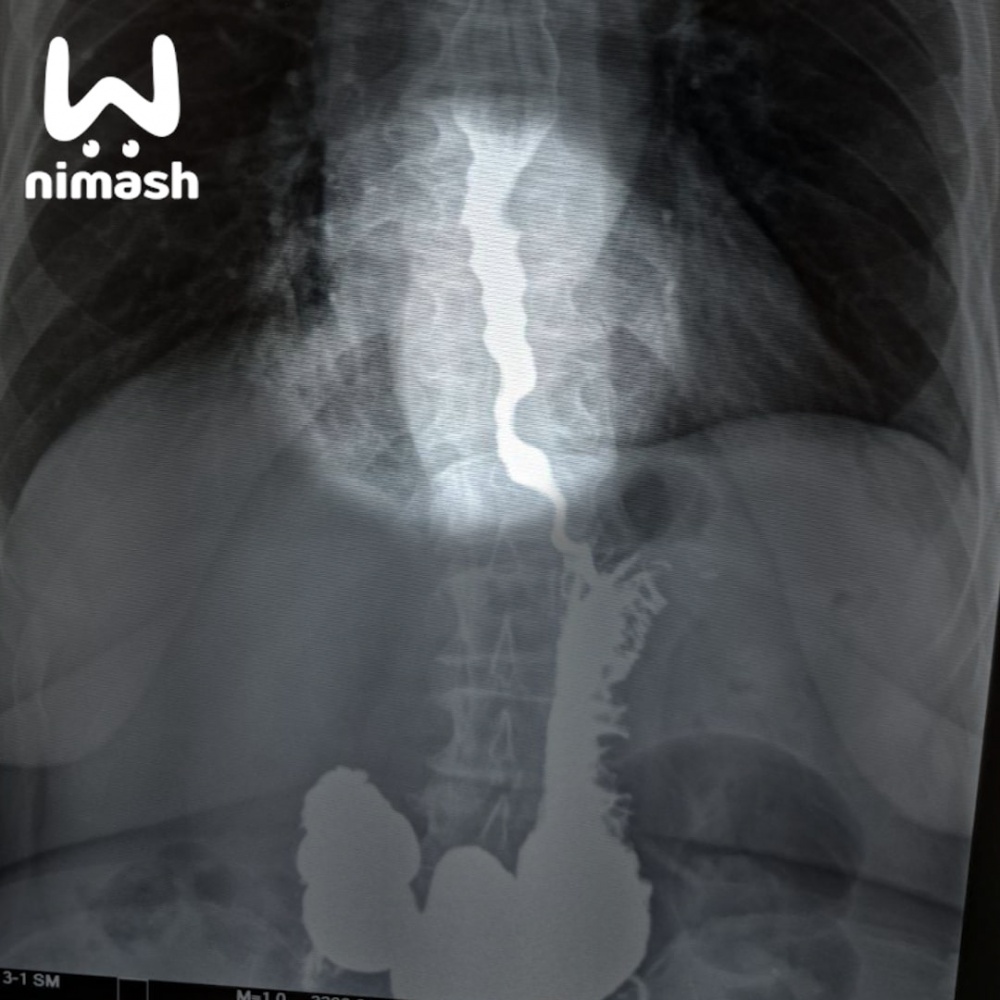

Пожилую пациентку, которая не могла есть и даже пить из-за редкой болезни, спасли хирурги ЦГБ Арзамаса. Они провели уникальную операцию по расширению пищевода.

У 70-летней пенсионерки нашли ахалазию — патологию, при которой орган сужается до аномальных размеров и не пропускает ни пищу, ни жидкость. Состояние стремительно ухудшалось, и врачи решились на операцию — первую такого рода в области. В пищевод ввели специальную пластиковую трубочку и плавно надули.

Сейчас пенсионерка уже может спокойно пить и есть жидкую пищу, позже трубку из организма уберут.